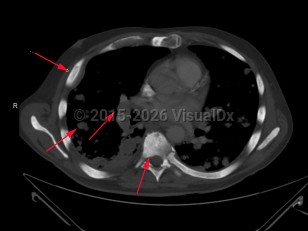

Metastatic prostate carcinoma

Prostate gland carcinoma that has disseminated. Metastatic prostate carcinoma is seen less frequently due to prostate-specific antigen screening, which enables early diagnosis of prostate cancer while it is still localized. Malignant cells can appear throughout the body as cancer advances, with the bones and lymph nodes more commonly affected.

In patients with bone metastasis, the axial skeleton is often involved. Common findings include bone pain, pathologic fracture, and spinal cord compression may be observed. Patients with lymph node involvement will present with regional or cervical lymphadenopathy. Masses may also be observed, especially in the neck. The skin, liver, and penis are also reported areas of involvement.

The findings of advanced prostate cancer include perineal pain, weight loss, and urinary changes such as frequency, retention, dysuria, and hematuria. Physical exam may reveal areas of induration, asymmetry, and/or prostate nodule. Risk factors include advancing age, family history, obesity, poor diet, elevated insulin levels, and vitamin E supplementation. More common in individuals of African descent.